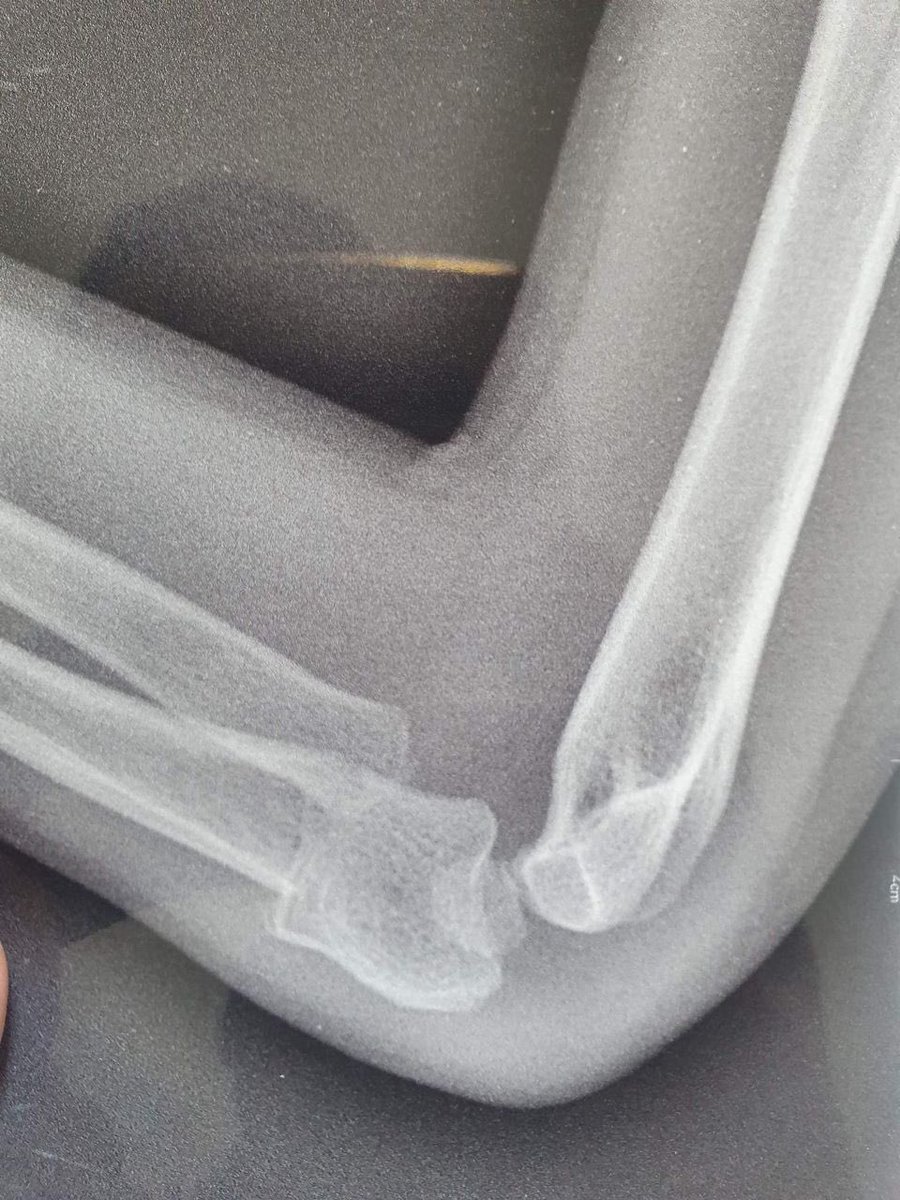

6-year-old child, post FD with Lt elbow swelling and pain.

What’s your further management? @Davembmd @DrBhavinJadav @Plexusorthoexam @Pranai_B @traumaticum @MatthewHarbMD @CPOrthopedics @pratikorho @ChrisGeeOrtho @itius @MGalanOlleros

@GwSafwan @Davembmd @DrBhavinJadav @Plexusorthoexam @Pranai_B @traumaticum @MatthewHarbMD @CPOrthopedics @pratikorho @ChrisGeeOrtho @itius @MGalanOlleros Closed reduction and i would prefer to add k-wire